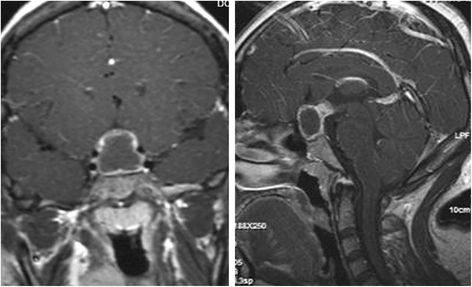

A 35-year-old female was admitted to our department presenting with headache, polyuria, fatigue and menstrual abnormalities for five months. Past medical and family history were unremarkable. Physical examination showed bitemporal hemianopsia. The preoperative endocrine levels in serum revealed insufficiency of the thyroid, gonadotropin and adrenal axes, with increased levels of prolactin. The urine volume per 24 h was about nine liters. A sellar contrast enhancement MRI was performed (Figs. 1, 2 and 3).

According to semiology, disease history and radiological characteristics, the patient underwent a craniotomy via subfrontal approach due to the initial diagnosis of hypophysial abscess. Intraoperatively, a sellar cystic lesion was noted with moderate vascular supply. Visualization of the lesion revealed yellow fraction pus within the cyst and milky-white wall (Fig. 4 left). After the lesion was resected, a histological examination revealed necrotizing granulomas composed of perinecrotic epithelioid histiocytes, lymphocytes and occasional multinucleate giant cells (Fig. 4 right).

The postoperative MRI showed the lesion was disappeared (Fig. 5). However, the symptoms of polyuria and hypopituitarism were still present. Fortunately, the patient responded well to a pharmacological dose of hormonal replacement. Dose reduction resulted in exacerbation of her symptoms after one year. Finally, we decided to administer long-term hormonal replacement to control her symptoms.

Case 2

A 57-year-old female was admitted to our department complaining of polyuria, weight loss and a menstrual disorder for the past 24 months. Past medical and family history were unremarkable. The preoperative serum endocrine levels revealed thyroid and adrenal axis insufficiencies, but increased of levels of prolactin. A sellar contrast enhancement MRI, regular cerebral MRI and plain brain X ray were performed (Figs. 6, 7 and 8).

All eight patients had a sellar mass extending into the suprasellar region that appearing on long T1, long T2 and contrast enhanced on MRI. The lesion typically demonstrated marked, homogenous enhancement (except case 1, 2), although heterogeneous (case 2) and ring-like enhancement (case 1) was also noted. An abnormally thickened pituitary stalk was noted in all patients, and the mean size of the seller mass in our patients was 15.3 mm in the longest diameter (summarized in Table 2).

Imaging characteristically demonstrates a sellar mass with a tongue-like, suprasellar extension. The lesion may contact or infiltrate the basal hypothalamus. Pituitary stalk thickening is often a prominent feature. The lesion usually shows marked, homogenous enhancement, although heterogeneous and ring-like enhancement may also manifest. However, enhancement with contrast in granulomatous hypophysitis is very variable and it can not be used as a reliable distinguishing feature with pituitary adenomas. And other most common findings are dural enhancement and sphenoidal sinus mucosal thickening.